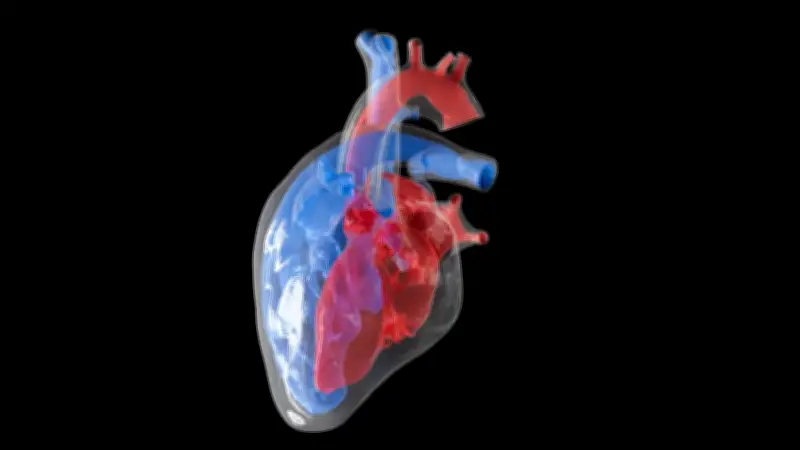

Une découverte surprenante sur le cancer du cœur

Le cancer du cœur est extrêmement rare, et une nouvelle étude publiée dans la revue Science explique pourquoi. Des chercheurs ont découvert que les battements cardiaques constants créent un environnement hostile à la formation de tumeurs. Cette découverte pourrait ouvrir la voie à de nouvelles stratégies de prévention et de traitement du cancer.

Les scientifiques ont observé que le mouvement rythmique du cœur empêche les cellules de se diviser de manière incontrôlée, un processus clé dans le développement du cancer. En laboratoire, ils ont constaté que les cellules cardiaques exposées à des contractions mécaniques régulières étaient moins susceptibles de développer des mutations cancéreuses. Cette protection mécanique est unique au cœur et pourrait expliquer pourquoi les tumeurs cardiaques primaires sont si rares.